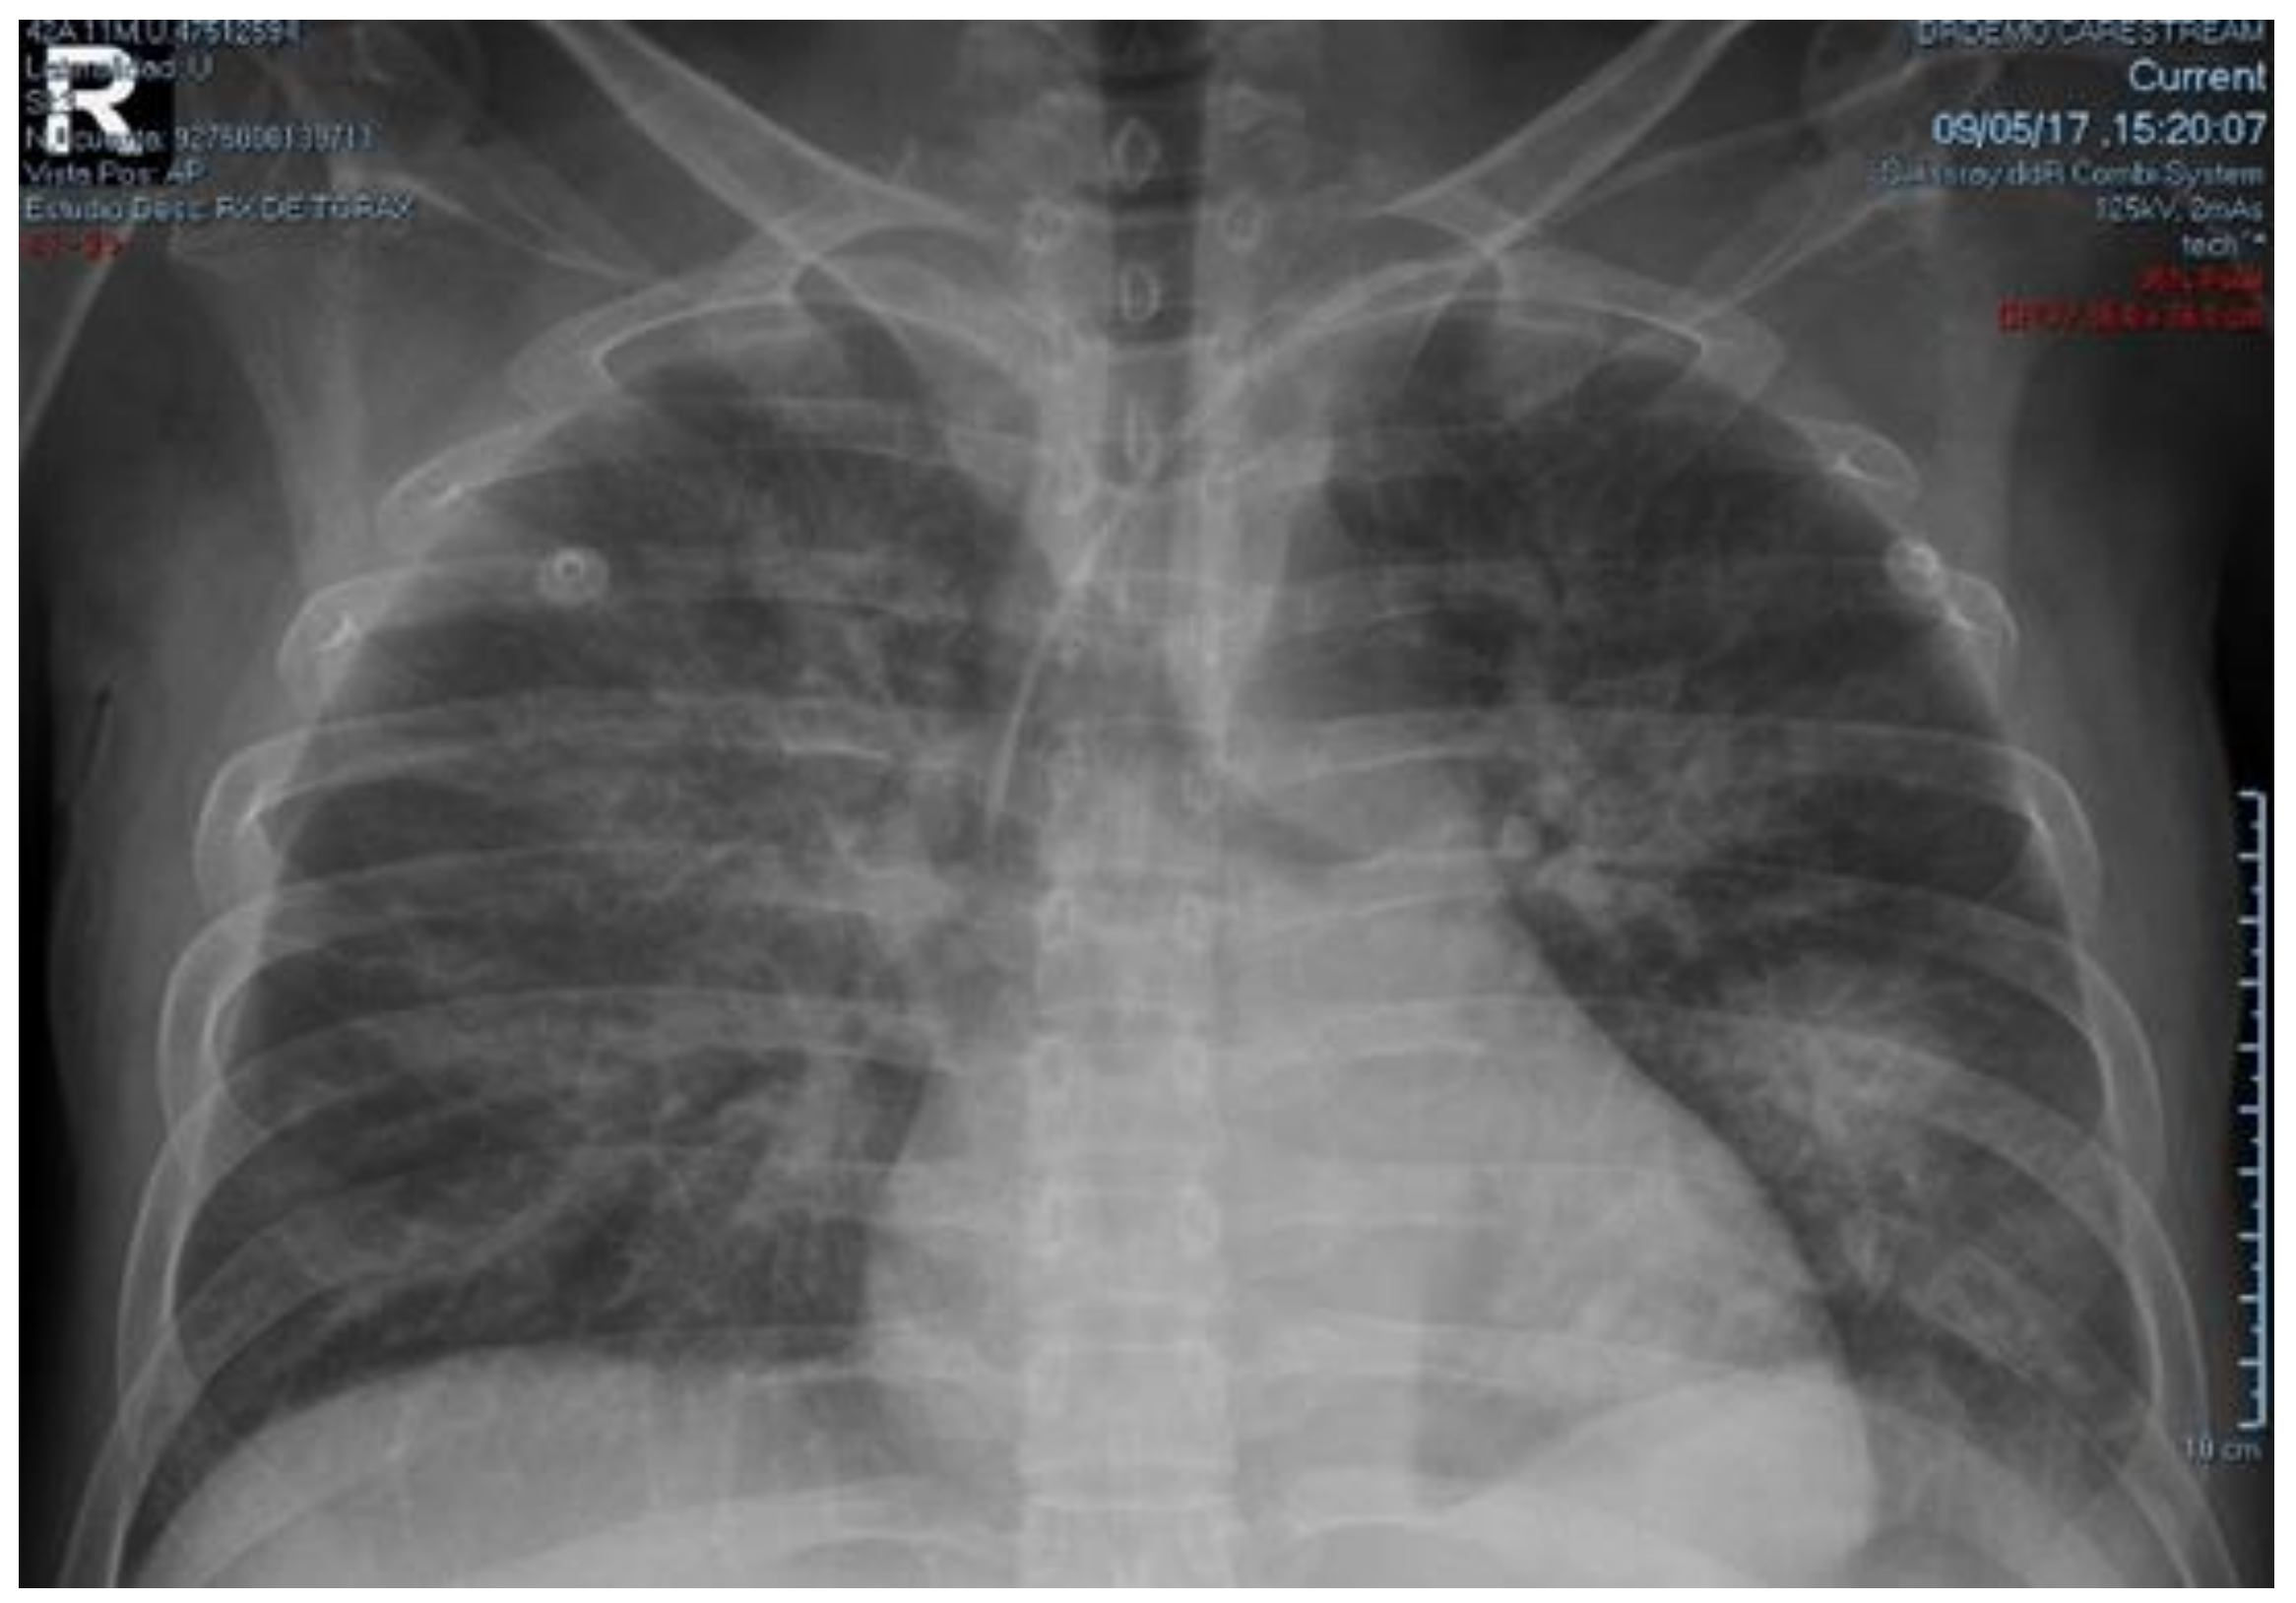

2. Case Presentation